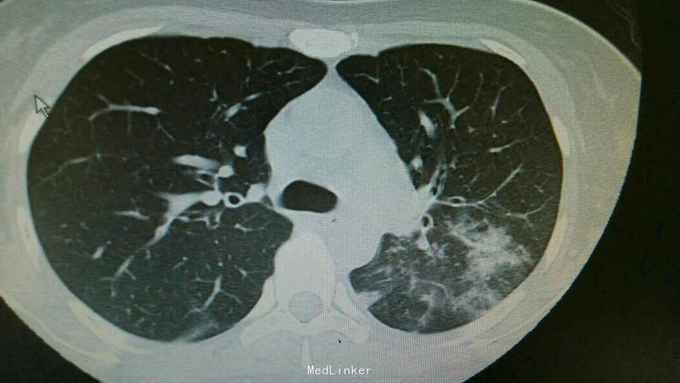

主诉:发热伴咳嗽咳痰6天。 病史:患者6天前无明显诱因出现发热,最高体温39.3度,伴有咳嗽,咳痰,咳黄色粘液痰,无畏寒寒战,无头晕头痛,为求治疗,入住我科。

查体:双肺呼吸音粗,双下肺可闻及湿罗音。心腹无异常。 辅查:双肺炎症,左侧可见多发斑片状,渗出实变影,边缘模糊,部分邻近胸膜,粘连。

诊断:肺炎支原体费炎。 治疗:入院予以抗感染,止咳化痰等治疗。治疗后复查胸片,左中下肺炎症好转。